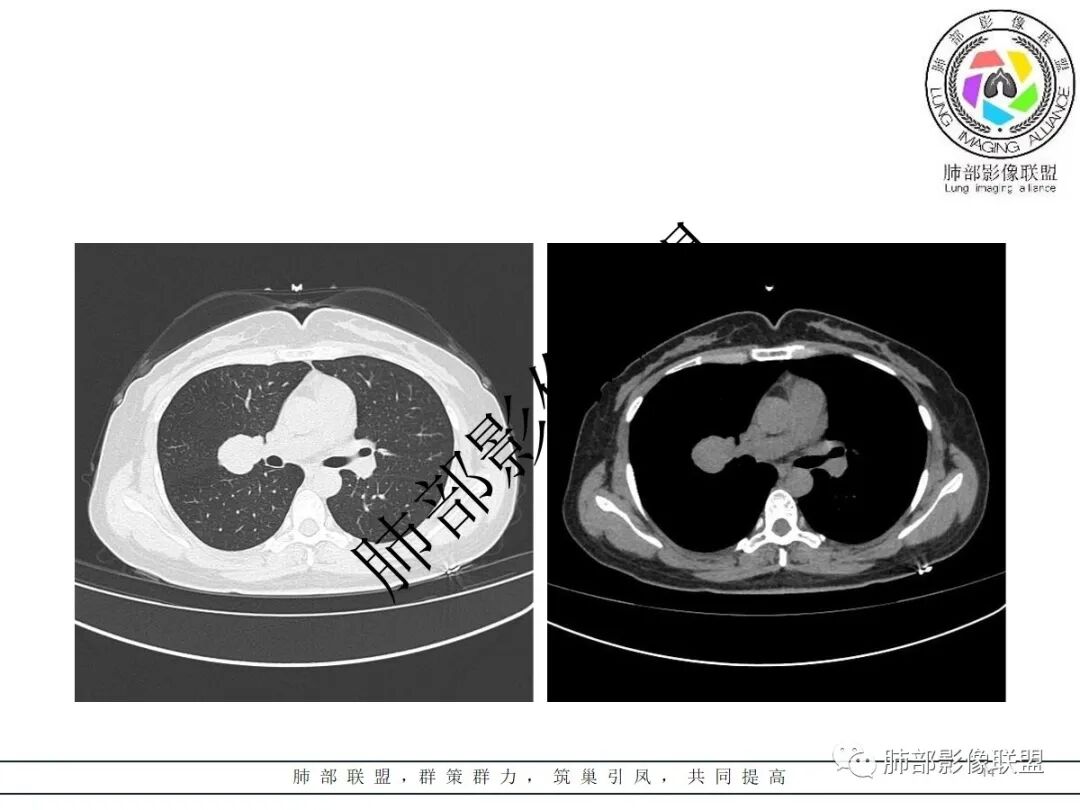

右肺门类圆形实性肿块,边缘光滑,无分叶毛刺,跨叶,推移血管,密度均匀,增强延迟强化相对明显,未见坏死及血管造影征。

跨叶裂,类圆形,有浅分叶,血管好像来源于肺动脉

支持SFT首选

PSP跨叶比较少,如果局部叶裂发育不良可以

2.右肺水平叶裂斜叶裂肺门交界区类椭圆形块影,表面光整,未见分叶毛刺及棘状突起,未见邻近结构牵拉。与邻近支气管无关联。

3.病灶密度均匀,未见液化坏死、钙化及脂肪低密度。轻度强化,可见纤细血管影蜿蜒穿行。右肺动脉推移变形,未见侵入或充盈缺损。

3. 良性病灶好发部位由外而内排个序:孤立性纤维瘤(SFT)、硬化性肺细胞瘤(PSP)、错构瘤、巨淋巴结增生症(CD)等。

4)发生于肺表面(近脏层胸膜或叶间裂),强化不显著,可见穿行血管,与本例的符合程度是最高的。